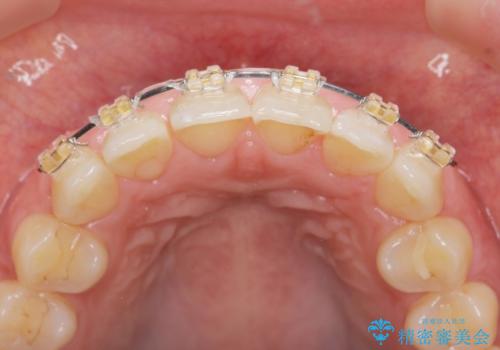

出っ歯に見える前歯の改善 部分ワイヤーとマウスピース矯正

- インビザライン +部分ワイヤー矯正

- 出っ歯に見える前歯の改善を希望され、来院されました。

マウスピースでは改善の難しい歯の動きを部分ワイヤー矯正で整えたのち、奥歯の噛み合わせや細かい歯の並びをマウスピース矯正インビザラインで整えていきます。

最終的な前歯の並びに大変満足いただくことができました。